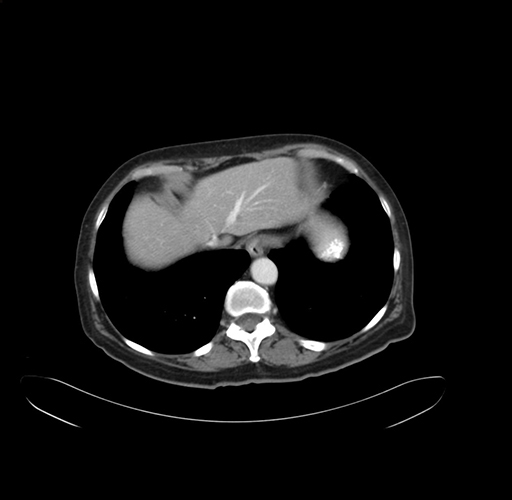

Pre-Chemo: Axial Venous